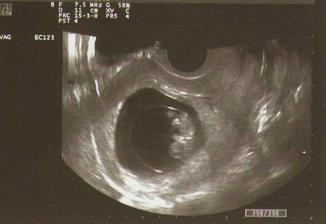

28.1.09 - další KO a PN (rizikové těhu) - dopadla výborně!!!

Mimi má krásných 2,9 cm, srdíčko mu tluče, mávalo na nás ručičkama(takže už se pohybuje),

má vše, co má mít a já jsem neskutečně šťastná.